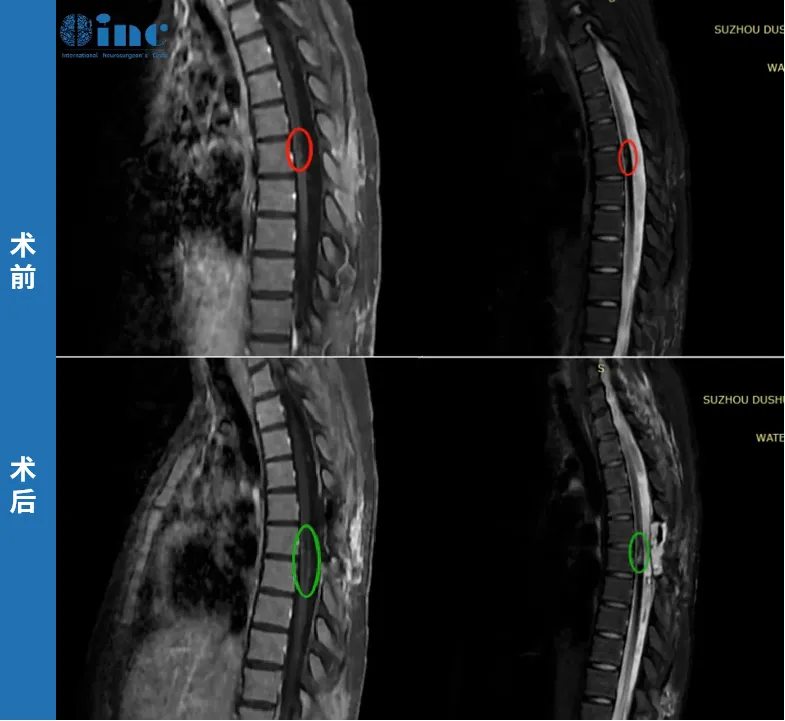

田田,21岁,一次常规体育运动后感到后背轻微疼痛,两天后出现双下肢无力。检查确诊为胸髓髓内出血性病变,病情进展迅速,随即出现排尿困难、双下肢无力持续加重等症状。进一步检查确诊为胸髓髓内海绵状血管瘤。当地医生判断血管瘤位置深且偏腹侧,手术风险高,术后大概率瘫痪,建议保守治疗。然而血管瘤再次出血,两天内症状急剧恶化,双下肢运动功能完全丧失,并出现大小便失禁。

巴教授的评估是:"上一次出血已经在脊髓内造成了严重损伤,血液就像管道中的液体一样,从出血部位沿脊髓纵向向上方和下方蔓延。手术能够在一定程度上改善术前已有的症状,但需要特别强调的是,并非所有症状都会因此消失,患者和家属必须对此有清醒的认识。此次手术的核心目标,是切除残余的血管畸形,防止未来再次出血引发更难以承受的后果。"

最终,巴教授在苏州大学附属第四医院为田田顺利完成了示范手术,术后未出现新发神经功能损伤,术前的严重症状也得到了一定程度的缓解。

这个案例说明:当疾病已经造成严重损害时,手术的意义不在于"逆转一切",而在于"防止更坏的事情发生"。家属在手术前需要建立合理的预期,不能以"术后恢复原状"作为唯一的衡量标准。